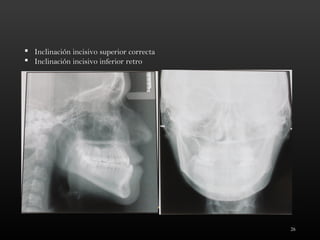

 Inclinación incisivo superior correcta

 Inclinación incisivo inferior retro